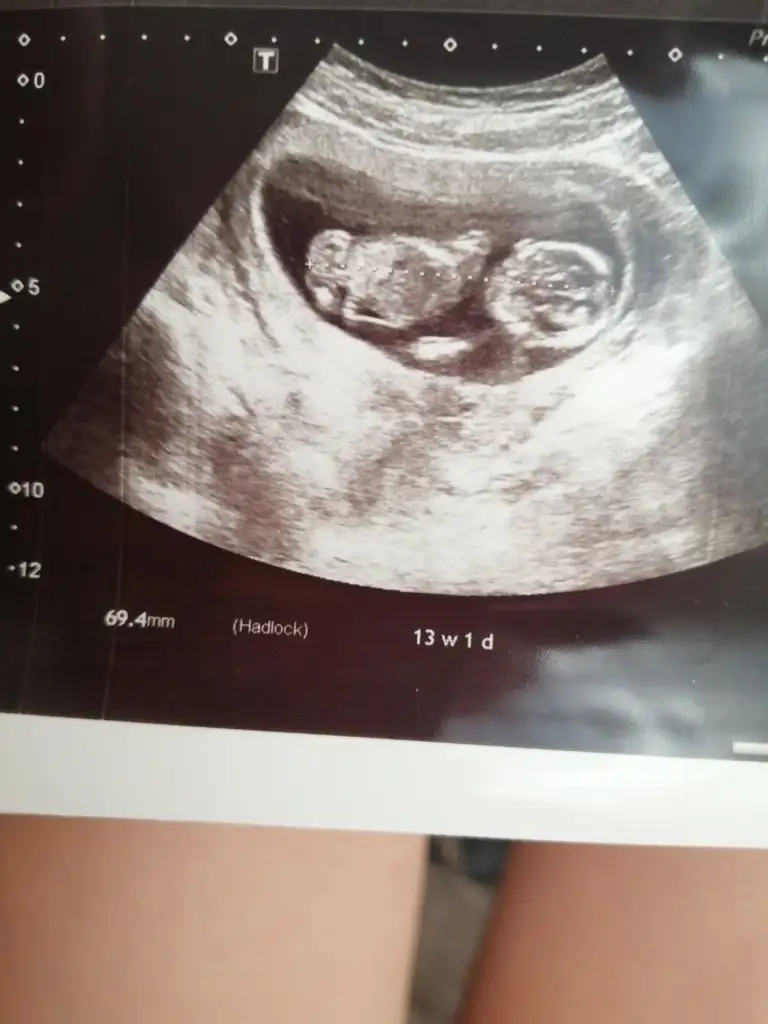

Merhaba, baş popo mesafesi 6.94 cm demek. Hayırlı olsun, sağlıkla kucağınıza alınMerhaba ilk defa böyle bir foruma üye oldum :) Şuan 13+1'deyiz. Cinsiyetini tam net olarak değil ama tahminen kız olarak belirledi :) Önümüzdeki Salı tekrar bakacak :)

CRL 69.4MM yazıyor bu ne anlama geliyor?

Crl bebeğin yaklaşık boyu baş popo mesafesi canım.Merhaba ilk defa böyle bir foruma üye oldum :) Şuan 13+1'deyiz. Cinsiyetini tam net olarak değil ama tahminen kız olarak belirledi :) Önümüzdeki Salı tekrar bakacak :)